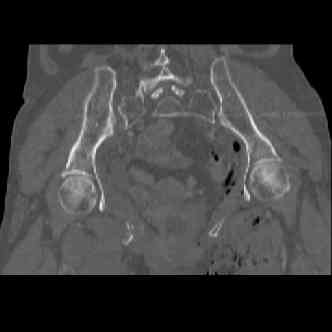

attached are images of a 70 year old female after peds versus car. her own car ran her over.

injuries are limited to the pelvis. left rami open and visible in a 10cm vertical laceration just lateral to left labia majora. wound is grossly clean. no vaginal and no urinary issues. CT scan shows widening of both SI joints anteriorly but I think this is vertically stable pattern.

pt treated that night with I/D and supra-acetabular frame to close the ring. consideration was given for SI screws bilateraly, but given time of night and other factors decision made not to proceed.

so the question is what next operatively if anything? concerns are infection, nonunion anteriorly and possible incompetence of the pelvic floor which may lead to prolapse issues. right rami are comminuted and plating may entail ilioinguinal approach to extend plate laterally to right iliac wing. retrograde screw up right rami is an option but I am not convinced it will add much. adding SI screws very doable, but major concern is restoring anterior ring. so far wound is clean and closed over a drain, and I have no plans to open it back up and wash again.

attached are several CT cuts. please let me know if you need more. the CT is pre-pelvic ex-fix placement.

Thank you.